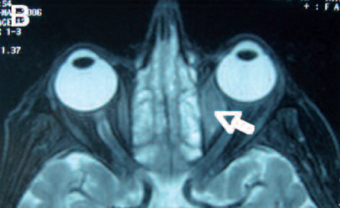

Orbital lymphoma is a common type of non-Hodgkin lymphoma that occurs near or on the eye. Common symptoms include decreased vision and uveitis. Orbital lymphoma can be diagnosed via a biopsy of the eye and is usually treated with radiotherapy or in combination with chemotherapy.

Primary visible signs of ocular lymphoma include proptosis and a visible mass in the eye. Symptoms are due to mass effect.